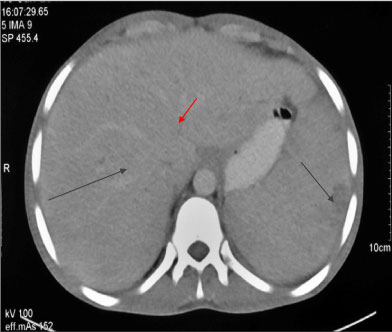

A sixteen-years-old laborer, with non-contributory past history, presented with fever, jaundice and unintentional weight loss of eight kilograms over two months. The patient had also noticed development of new lesions over his face and trunk. Clinically patient was thin build (BMI-16.4 kg/m2), febrile (39 °C), had non-tender, generalised lymphadenopathy (cervical, axillary and inguinal), warty plaques over face and trunk (Figure 1) with hepato-splenomegaly. Investigations revealed haemoglobin-6.4 g/L, leukocytosis (11.4 × 109/L- 94% neutrophils) and normal platelets. Viral markers including HIV-1 and 2 were negative with CD4 count of 564 cells/mm3. Tuberculin sensitivity test was non-reactive (0 mm). Lymph node biopsies (cervical and inguinal) showed granulomatous reaction and Alcian blue stain revealed blue coloured capsule consistent with cryptococcosis. Further Ziehl Neelsen stain for acid-fast bacilli, mycobacterial PCR and gene Xpert were negative from the specimen. Biopsy from skin lesion also revealed cryptococcal infection and blood was incubated in BACTEC aerobic and anaerobic culture bottles. After five days of incubation, growth was noticed and subsequent sub- cultures were done on blood agar, chocolate agar and Mac Conkey agar. After two days of inoculation, colonies from blood agar revealed gram positive round budding yeast cells. Colonies were further sub-cultured on Saboraud’s dextrose agar, Christensen’s urea and birdseed agar. Colour of the slant in Christensen’s media turned to magenta in one day establishing urease production by the organism and demonstration of brownish colonies on birdseed agar, further established characteristic phenol oxidase production by Cryptococcus neoformans. Patient also had obstructive jaundice (total and conjugated bilirubin of 10 mg/dL and 7.8 mg/dL respectively) with raised ALP (1954 IU/L) and GGT (358 U/L). Contrast enhanced CT showed generalized (mediastinal, abdominal, inguinal) lymphadenopathy, intrahepatic biliary duct dilatation, hepato-splenomegaly with multiple hypoechoic lesions (Figure 2). Initially jaundice was attributed to obstruction by peri-portal lymphadenopathy, however endoscopic ultrasound and MRCP suggested sclerosing cholangitis and consequent autoimmune hepatitis workup (including ANA, AMA and ASMA) was negative. Further immunodeficiency work-up including immunoglobulin profile, Nitro Blue tetrazolium test, T and B lymphocyte counts and NK cell counts were normal for age. Flow cytometry for expression of IL12Rβ1 was performed on peripheral blood mononuclear cells following stimulation with phytohemagglutinin and culture for 72 hours. Expression of IL12Rβ1 on gated CD3+ T lymphocytes was reduced compared to control (Figure 3). Targeted next-generation sequencing was performed using a custom designed gene panel comprising of 44 common primary immunodeficiency disease genes which include four genes (IFNGR1, IFNGR2, IL12RB1 and STAT1) associated with MSMD phenotype on the IONS5 platform from Thermo Fisher Scientific. No pathogenic variants were found in IL12RB1 or other genes associated with MSMD. All exons of the IL12RB1 were well covered and no deletion (homozygous or heterozygous) were noted. Patient was initially managed with conventional amphotericin (1 mg/Kg; cumulative 4.5 g over 6 weeks) and flucytosine (25 mg/Kg), along with antibiotics for cholangitis and later switched over to suppressive prophylaxis with fluconazole. His jaundice improved following anti-fungal therapy and liver function tests normalized by second month of follow-up and lymph nodes as well as skin lesions (Figure 4) also had regressed significantly by six months.

Figure 2: CECT abdomen showing multiple hypoechoic lesions in liver and spleen (black lines) along with intrahepatic biliary duct dilatation (red line). View Figure 2